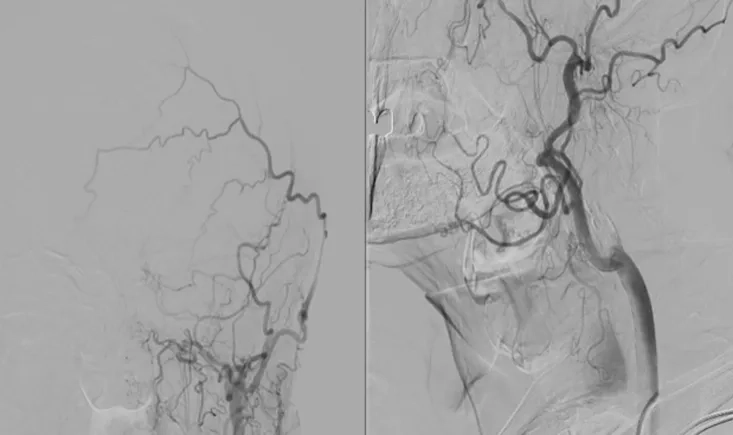

This PVI 2025 symposium replay examines post-CREST-2 carotid stenting through the case of a 71-year-old wom…